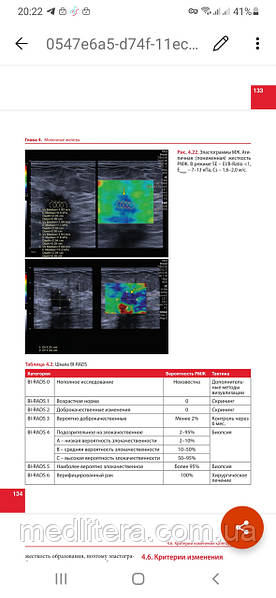

У монографії розглянуті питання застосування ультразвукової еластографії в клінічній практиці з урахуванням актуальних практичних і клінічних рекомендацій. Детально описана методика проведення еластографії різних внутрішніх і поверхнево розташованих органів, принципи інтерпретації результатів, чинники, що впливають на конкретний результат і ефективність, коректність і відтворюваність кількісних і якісних показників еластоографії.